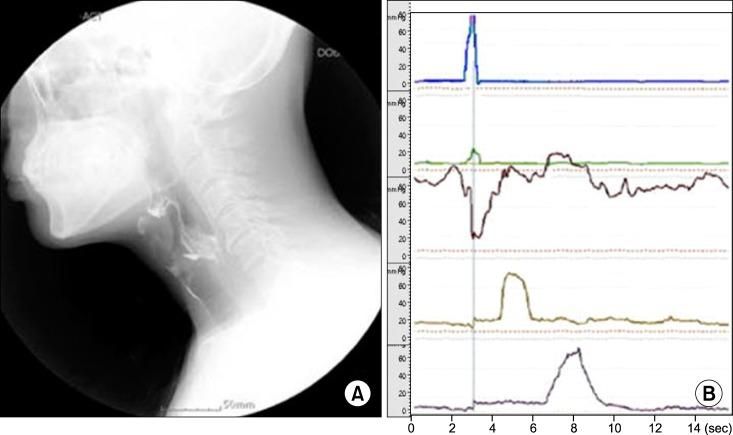

Videofluoroscopic swallowing study (VFSS) used for the diagnosis of dysphagia has limitations in objectively assessing the contractility of the pharyngeal muscle or the degree of the upper esophageal sphincter relaxation. With a manometer, however, it is possible to objectively assess the pressure changes in the pharynx caused by pharyngeal muscle contraction during swallowing or upper esophageal sphincter relaxation, hence remedying the limitations of VFSS. The following case report describes a patient diagnosed with lateral medullar infarction presenting a 52-year-old male who had dysphagia. We suggested that the manometer could be used to assess the specific site of dysfunction in patients with dysphagia complementing the limitations of VFSS. We also found that repetitive transcranial magnetic stimulation was effective in treating patients refractory to traditional dysphagia rehabilitation.